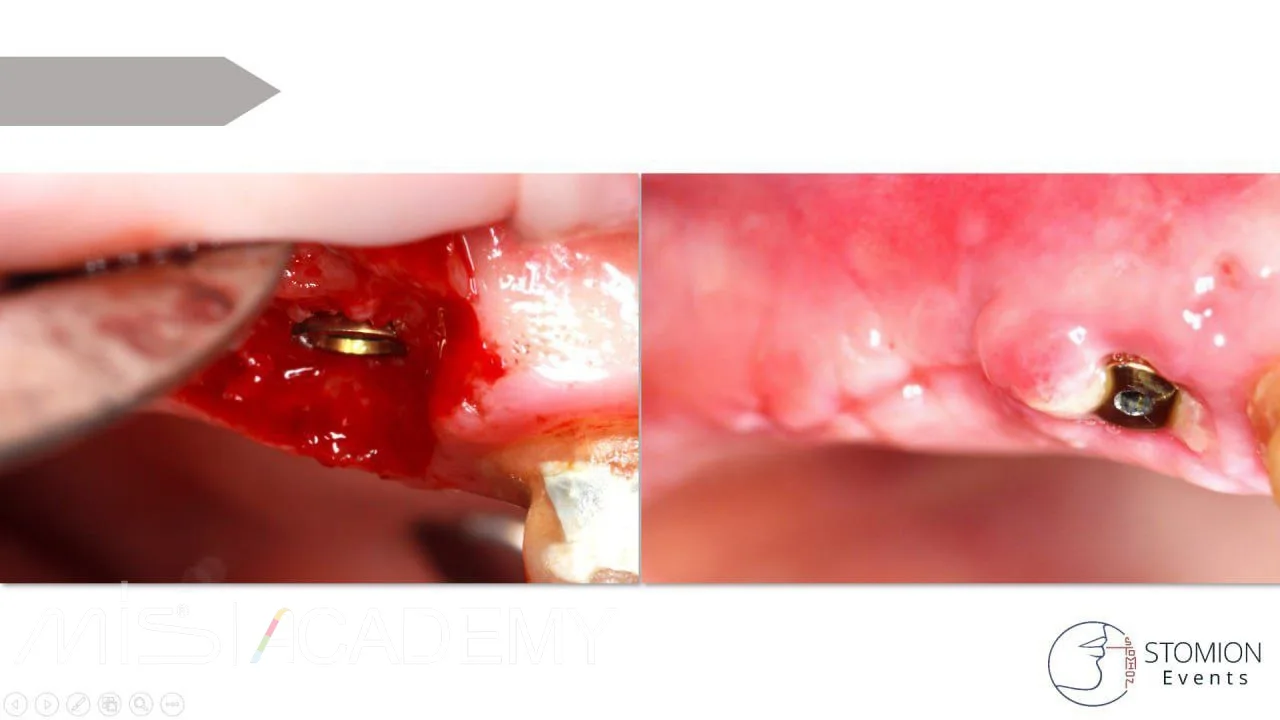

— Проведена имплантация MIS C1 в позициях 1.4, 1.6.

— На имплантаты установлены коннект абатменты.

— Особенности операции в области 1.6:

Выполнена операция транскрестального синус-лифтинга (ТКСЛ). Высота нативной кости в области шейки имплантата составляет 2-2,5 мм. Дно гайморовой пазухи приподнято на 8 мм. Уложен остеопластический материал Bio-Oss S. Вариант без костного материала был возможен, однако для данной высоты подъема дна пазухи было принято решение о перестраховке с использованием костного графта.